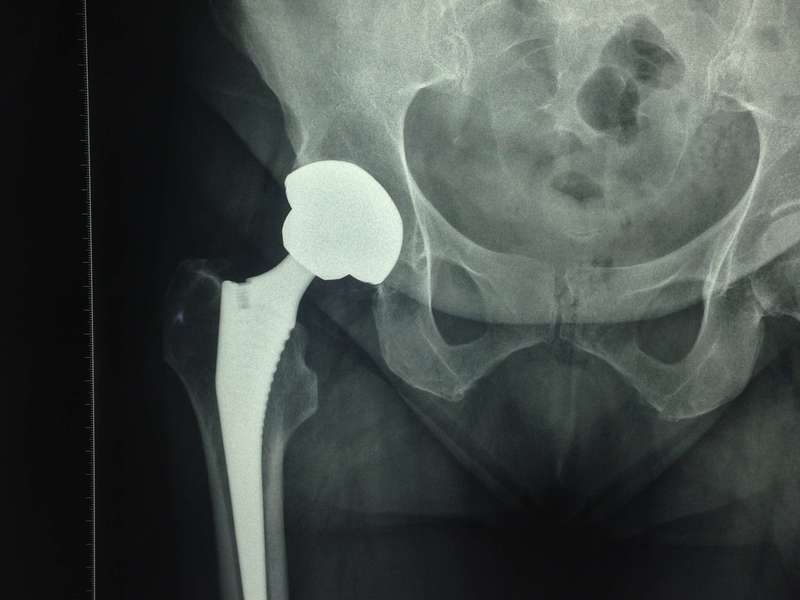

Pour un premier rendez vous, il est préférable de venir avec des examens radiographiques, prescrits par le médecin traitant, en fonction de la pathologie et de l'articulation concernées.